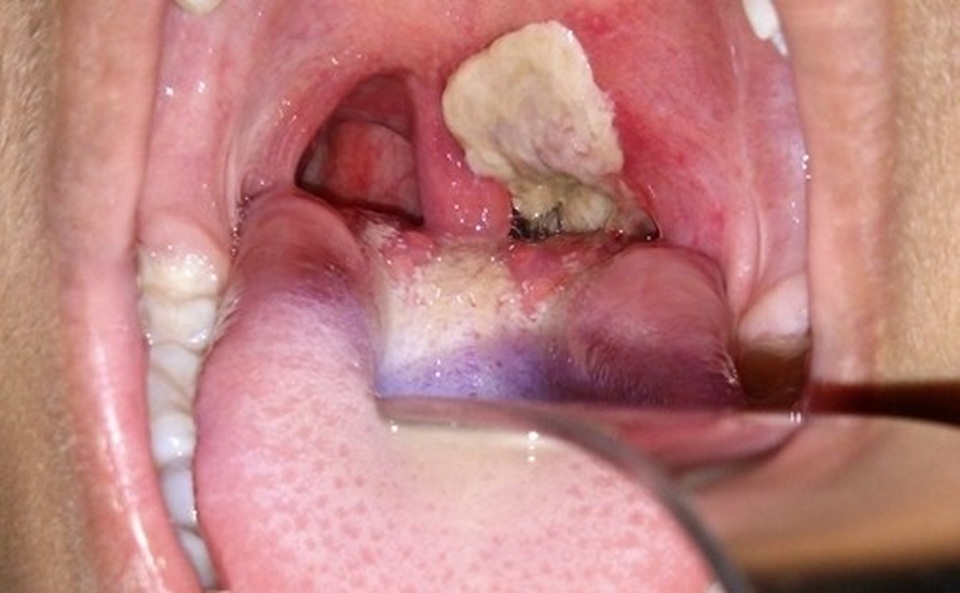

Phân tích chuyên môn của BS Phan Tứ Quý chỉ ra: “Bệnh bạch hầu thường có biểu hiện sốt nhẹ, đau họng dễ nhầm lẫn với các bệnh lý cảm cúm thông thường. Biểu hiện đặc trưng của bạch hầu là tình trạng người mắc bệnh có mảng trắng trong vùng hầu họng, mảng bám này dai, khó tróc. Những trường hợp mắc bạch hầu ác tính bệnh nhân sẽ có thêm các triệu chứng, hai bên cổ sưng to, vẻ mặt lừ đừ của tình trạng nhiễm trùng, nhiễm độc. Những biến chứng nguy hiểm khác là suy thận cấp, viêm cơ tim, rối loạn nhịp thường khiến bệnh nhân đột ngột tử vong.